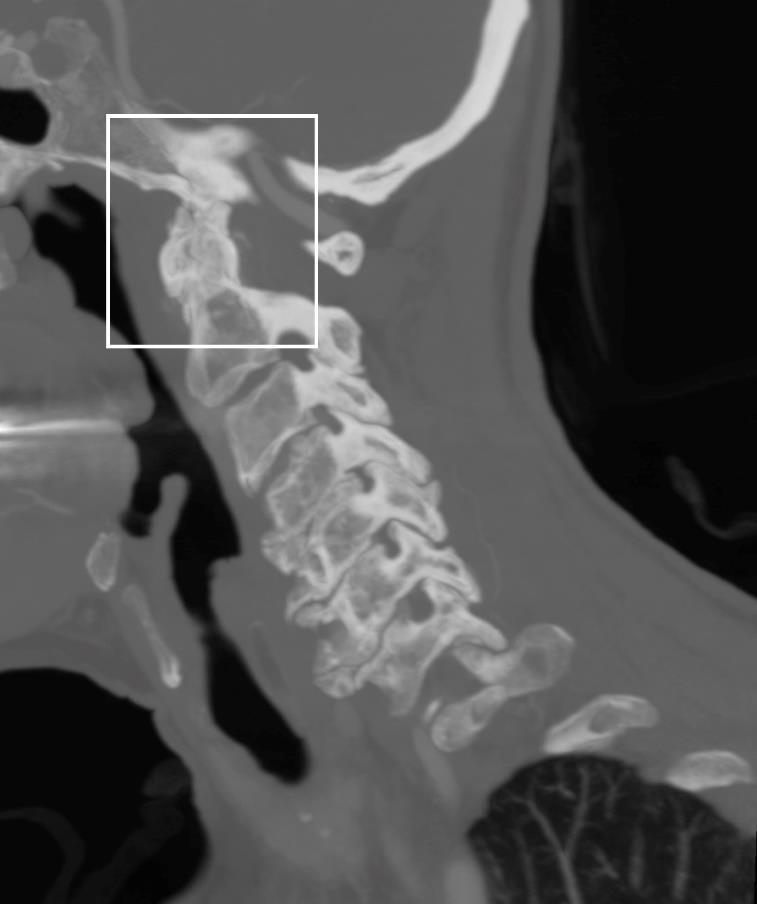

381 A Diagnosis Fit for a Queen: Crowned Dens Syndrome

EN Dankert Eggum, SA Schroeder Hevesi, B Sandefur

10.SnyderAandSchmalzleSA.Spontaneous Streptococcuspyogenes pelvicinflammatorydisease;casereportandreviewoftheliterature. IDCases. 2020;20:e00785.

Section Editor: Lev Libet, MD